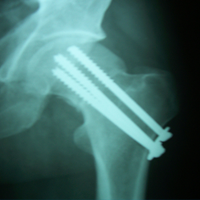

Case:7 Fracture Neck Femur with Implant failure and Re-Fixation with hemi-arthroplasty

Alcoholic Gardener by profession had slipped in bathroom & fell. He sustained fracture neck femur.He was operated with closed reduction & CC Screw fixation under IITV. Two weeks’ post fixation he again fell & sustained fracture in sub trochanteric region. He was treated with Hem-Arthroplasty with Tension band wiring.

Pre-Op

Post-Op

Post Fall

Oblique-Post Fall

Lat-Post Fall

Lateral-Post Prosthesis Fall

Post Prosthesis Fall

Post Uninon-3Months